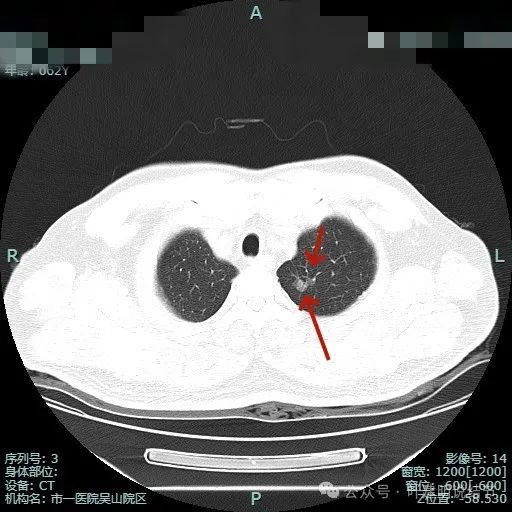

薄层影像:

病灶出现,瘤肺边界清,表面不平有分叶。

灶内密度不纯,整体轮廓清,瘤肺边界清楚。

明显分叶以及血管贴边并有异常增粗。